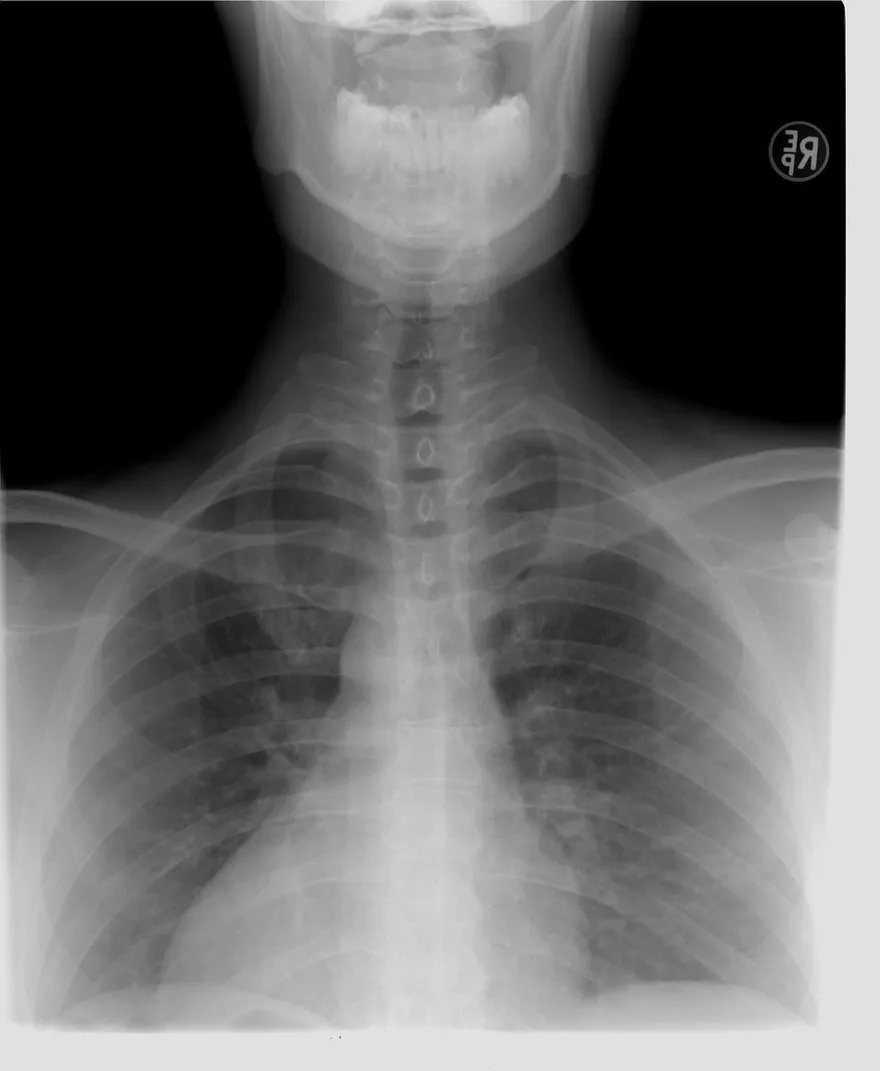

肋骨骨折

跌倒受傷

胸部外傷

隱形傷害

呼吸困難

連枷胸

氣胸

血胸

肺炎併發症

肋骨固定手術

深呼吸訓練

肺泡塌陷

骨折就醫